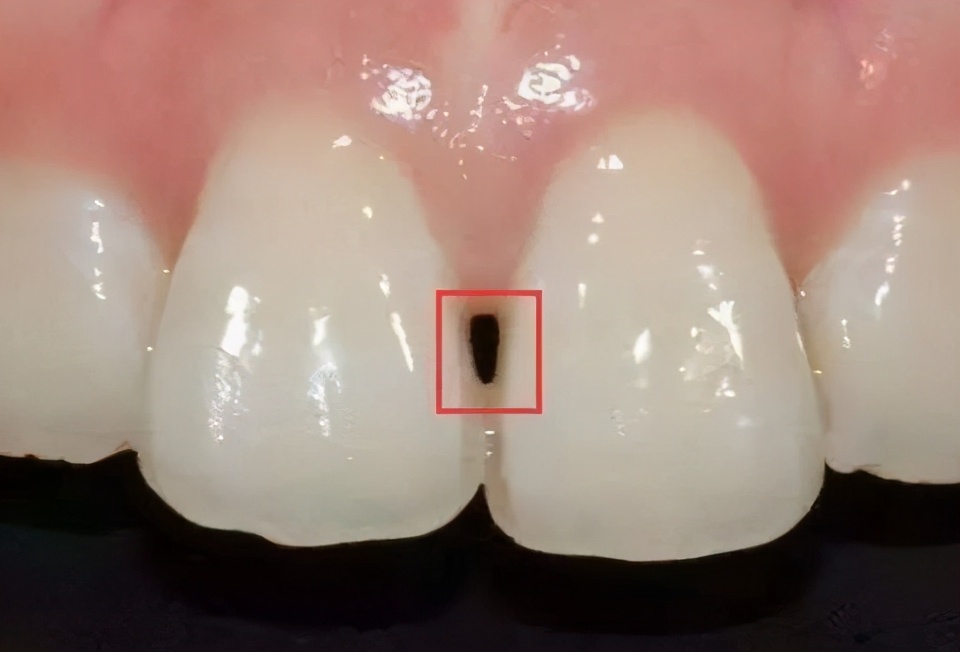

如果有黑三角症状的患者,会在吃饭时容易塞牙并且影响美观,尤其是门牙,呲牙一笑黑三角就明显可见!

顾名思义,这所谓的“黑三角”就是相邻的两颗牙之间不够贴合,从而形成的一个呈三角形状的空隙。

1、出现"黑三角"会导致说话漏风,且极大的影响牙齿美观,尤其是如果刚好发生在门牙,对于面容较大。